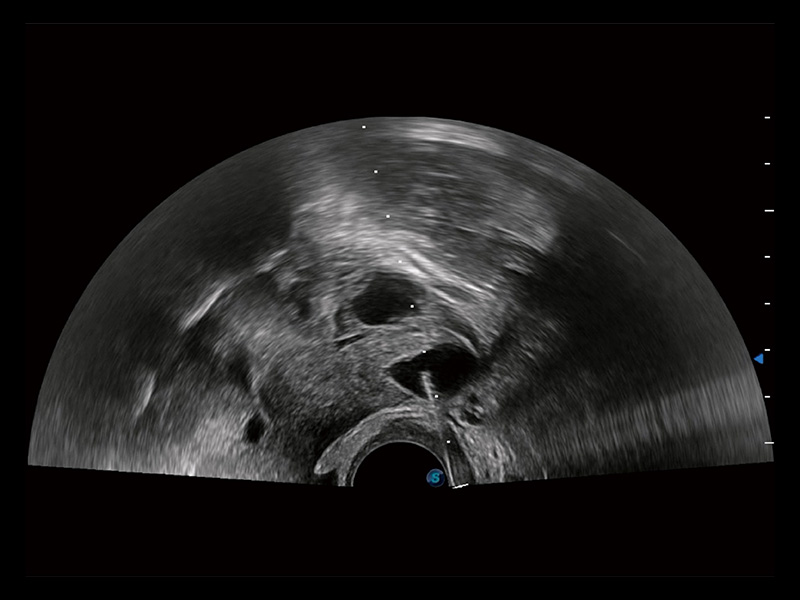

临床图

超声引导下双侧卵巢穿刺取卵

卵巢多囊样改变